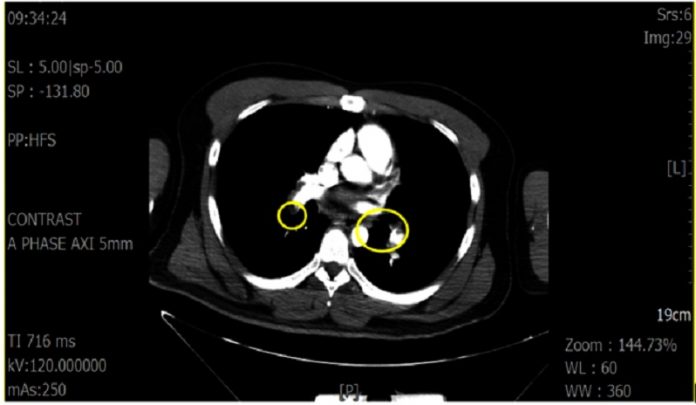

蔡昌宏表示,這名28歲男性在上班途中突感身體不適、盜汗,一路撐到公司門口即癱軟倒地,同事幫忙打119送抵醫院時,雖有意識,但臉色蒼白、全身無力、血壓低,說不出哪裡不舒服,經檢查發現有動脈血液缺氧現象,立即給予高濃度氧氣等緊急處置,並會診心臟內科,經電腦斷層檢查確診為肺栓塞,轉加護病房治療,一週後康復出院。